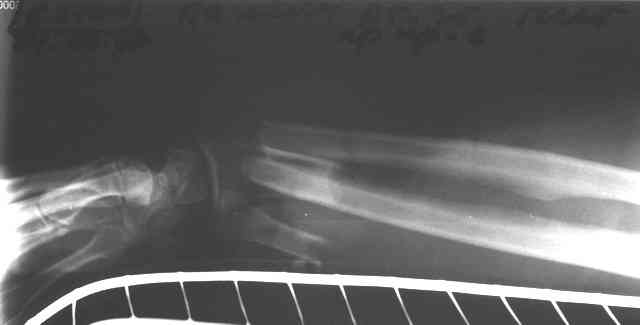

Травма 24 Октября этого года. Диагноз: Неполный травматический отрыв

нижней трети предплечья. Выполнено: ПХО открытого перелома, фасциотомия,

ЧКДО, шов лучевой артерии.

Спустя месяц выполнена резекция 2,5 см некротизированного конца

проксимального отломка лучевой кости. На сегодняшний день по ладонной

поверхности предплечья с переходом на наружний край имеется рана с

дефектом мягких тканей, выполненная грануляциями с дна и с краев.